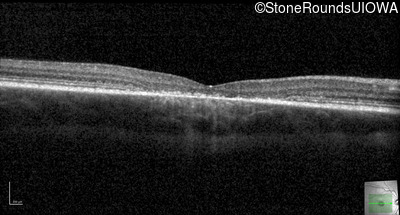

Age at visit: 13 years

This 13 year old male first had difficulty reading print and road signs in the past year.

Age at visit: 13 years (Visit 2)